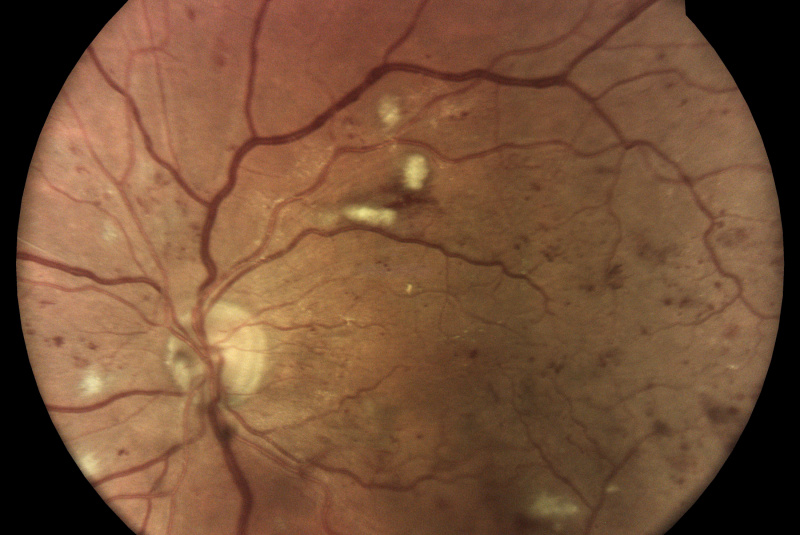

Technologie TrueColor Confocal společnosti iCare překonává limity běžných zařízení pro zobrazování fundu a SLO (scanning laser ophthalmoscop) tím, že kombinuje nejlepší výhody obou. Jednoduše řečeno, fundus kamery poskytují vysokou barevnou věrnost a SLO systémy vytvářejí vysokou ostrost, jasnost, celkovou přesnost a detailnost snímků. Když se tyto vlastnosti zkombinují, vznikne špičkový obraz sítnicové krajiny ve věrných barvách.

Pro diagnostiku a sledování běžných patologií, jako je diabetická retinopatie, musí být zařízení pro zobrazování očního pozadí schopna kombinovat vysoké rozlišení, vysoký kontrast a vysokou barevnou věrnost. To umožňuje zachytit drobné rysy a detaily a rozlišit jednotlivé změny, které byste jinak mohli snadno přehlédnout. Zatímco standardní systémy SLO mají vysokou jasnost, ostrost a kontrast, tradiční fundus kamery nabízejí vysokou barevnou věrnost, běžná zobrazovací řešení tyto dvě věci nekombinují!

Monochromatické lasery používané ve standardních SLO systémech mohou díky konfokálnímu optickému mechanismu poskytovat vysoce ostré a kontrastní snímky. Na druhou stranu však nedokážou zachytit sítnici v jejích skutečných barvách.

Systémy pro zobrazování fundu vytvářejí snímky přirozených barev pouze tehdy, pokud používají bílé světlo: to znamená, že v osvětlovacím paprsku používaném k zobrazení sítnice jsou přítomny všechny vlnové délky viditelného spektra. Na získaném snímku lze rozlišit různé barevné detaily.

Naproti tomu systémy využívající monochromatické zdroje světla, jako jsou systémy SLO, používají k osvětlení sítnice pouze určité vlnové délky. Poskytují proto pseudobarevné obrazy, které postrádají některé spektrální složky, a výsledkem jsou chybějící informace nebo barevné artefakty.

Systém iCare se vyznačuje použitím bílého LED světla v kombinaci s konfokální optikou, což pomáhá získat vysoce kvalitní snímky sítnice se zvýšenou barevnou věrností.